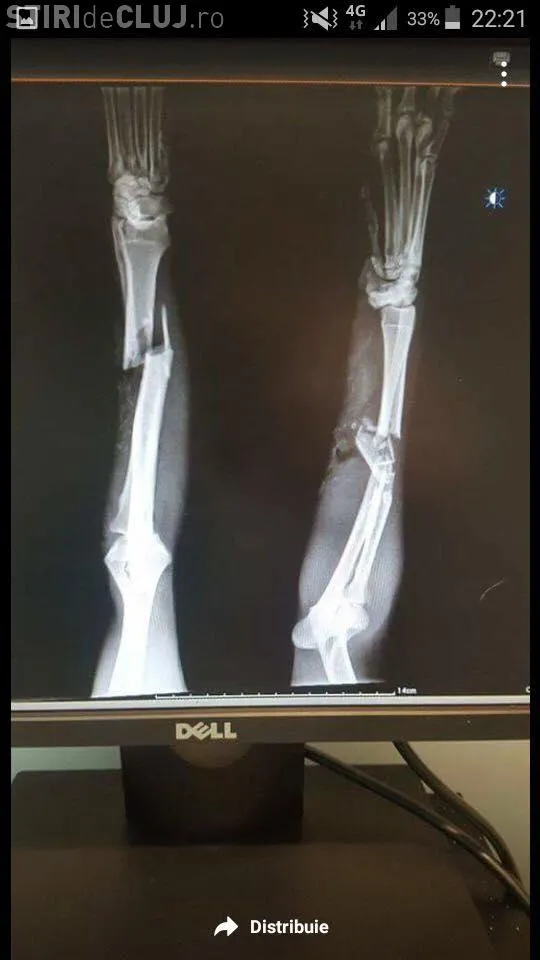

”Buna ziua! Din nou postez niște imagini care ne rup sufletul celor iubitori de animale! Acesta cățelușa se numește HOPE și are vârsta de 10 ani! A suferit enorm, a fost lovită de nenumărate ori cu obiecte masive peste piciorușe încât a ajuns in situația de a suferi 2 operații foarte costisitoare ( 56 de milioane, in jurul acestei sume +,-) momentan a fost operata este bine, sub tratament și multă dragoste! Acesta cățelușa a fost salvata de doamna Maria Tosa ea se ocupa de acest caz și la rugămintea altei doamne cu suflet mare încercam sa mai strângem bănuți Pentru a achita operațiile ... câte 1 leu dacă donam fiecare ajutam acest catel și pe doamna care se ocupa de acest caz ... pentru ca are alți catei in grija și nu își permite plata operațiilor! Sau donat in jur de 800 de lei pana in momentul de fata dar nu este de-ajuns ... așa ca va rog sa ajutați și acum , repet cu 1 leu de fiecare ajutam acest suflet!! Mulțumesc anticipat!! Contul și restul detaliilor se afla in una din pozele de mai jos!”, potrivit paginii Protecția Animalelor Cluj.